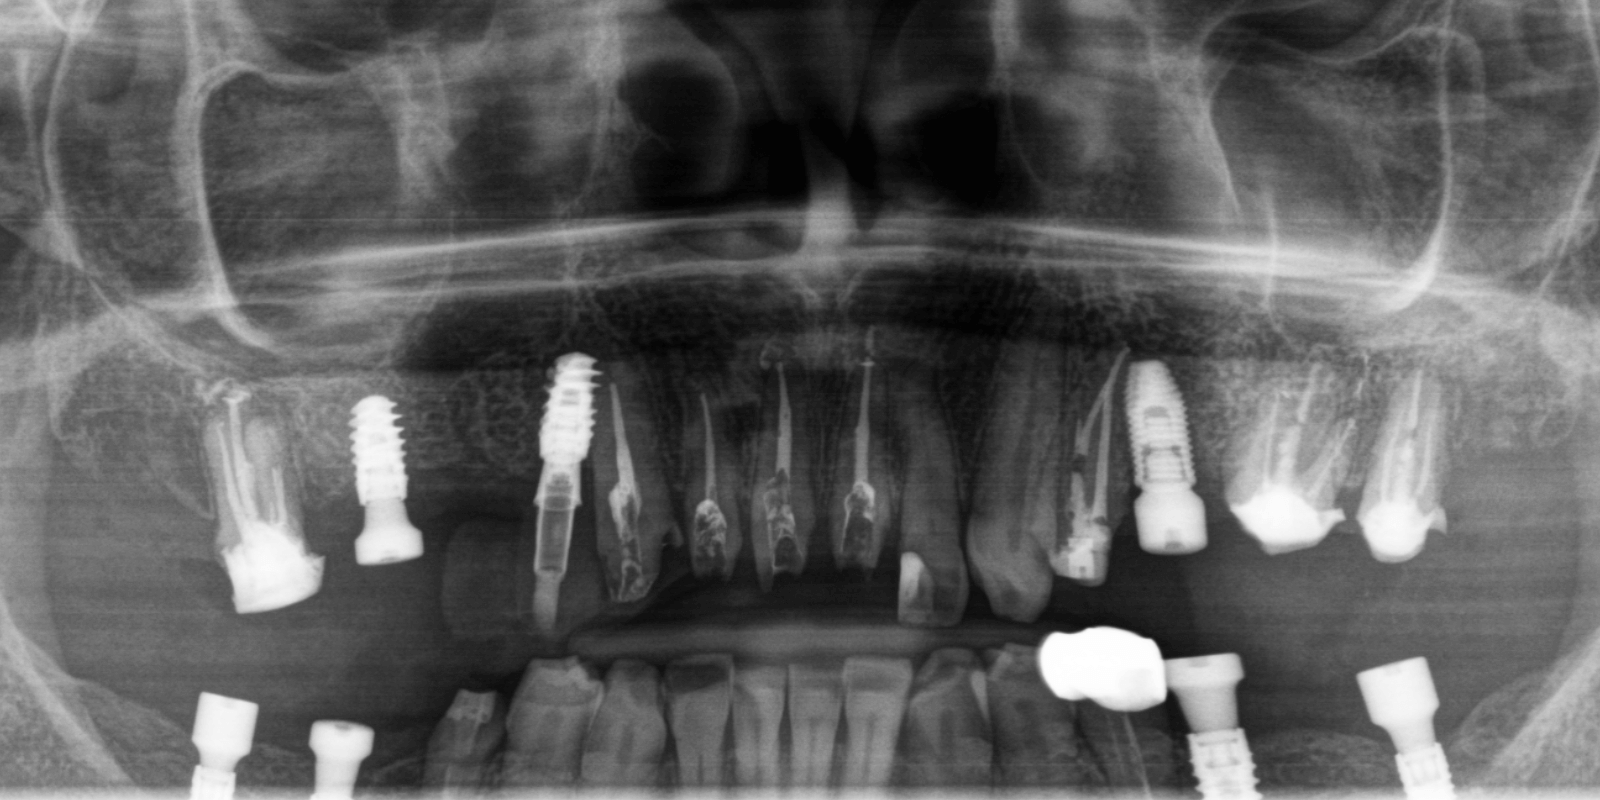

На верхней челюсти снять мостовидные протезы и удалить 4 зуба. Выполнить повторное лечение корневых каналов ("реэндо"). Также установить импланты Straumann BLX.

Во фронтальном участке улыбки, на зубах 21-13 снять одиночные коронки и одноэтапно провести эндодонтическое лечение. Работу по протезированию выполнить путем перенесения mock-up модели.

Фронтальный участок зубов выполнить керамическими ортопедическими конструкциями. Это был сложный случай, но абсолютно реальный для нашей команды. Мы составили индивидуальный план лечения, разделили его на этапы, учли временные возможности пациентки (которая жила не в Киеве) и выбрали протокол, позволявший максимально сохранить и восстановить.

Нижняя челюсть

Верхняя челюсть

Зона улыбки